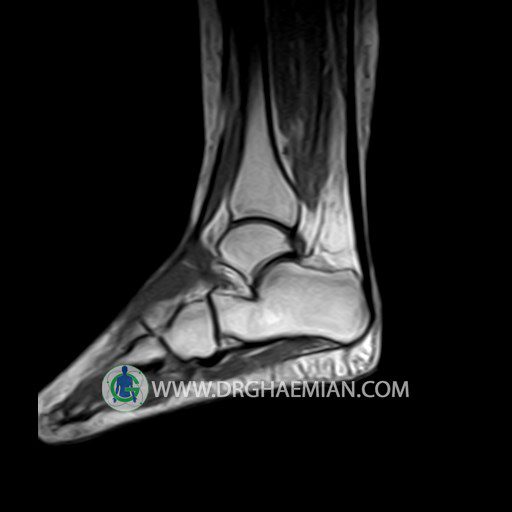

پزشکان اغلب از تصویربرداری ام آر آی برای تشخیص و درمان عارضه های پزشکی که فقط با استفاده از اشعه ایکس یا میدان مغناطیسی و امواج رادیویی قابل مشاهده است، استفاده می کنند. دستگاه ام آر آی تصاویر دقیق از ساختار های داخلی بدن ایجاد می کند. در این کیس تورم مچ پا بیمار مشاهده می شود.

Technique: Sagittal T1, T2 , Axial GE , coronal & sagital fatsat .